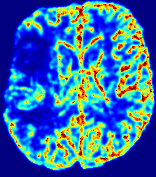

LesionRefer to captionRefer to captionRefer to captionRefer to captionRefer to captionRefer to caption𝐕rgbsubscript𝐕𝑟𝑔𝑏{\bf{V}}_{rgb}Refer to captionRefer to captionRefer to captionRefer to captionRefer to captionRefer to caption𝐕2subscriptnorm𝐕2{\|\bf{V}}\|_{2}Refer to captionRefer to captionRefer to captionRefer to captionRefer to captionRefer to captionRefer to caption3.53.53.52.82.82.82.12.12.11.41.41.40.70.70.70.00.00.0(mm/s)𝑚𝑚𝑠(mm/s)D𝐷DRefer to captionRefer to captionRefer to captionRefer to captionRefer to captionRefer to captionRefer to caption0.0200.0200.0200.0160.0160.0160.0120.0120.0120.0080.0080.0080.0040.0040.0040.0000.0000.000(mm2/s)𝑚superscript𝑚2𝑠(mm^{2}/s)Slice #1Slice #2Slice #3Slice #4Slice #5Slice #6

Figure 4: PIANO feature maps for another patient in the ISLES 2017 training set, where the lesion is located in the right hemisphere. Top row: segmented stroke lesion region (white) on different slices. The corresponding slices for the PIANO feature maps are shown in the following rows.

For a better insight into an estimated velocity field 𝐕𝐕{\bf{V}} and diffusion field 𝐃𝐃{\bf{D}}, we compute the following maps: (1) 𝐕rgbsubscript𝐕𝑟𝑔𝑏{\bf{V}}_{rgb}: Color-coded orientation map of 𝐕=(Vx,Vy,Vz)T𝐕superscriptsuperscript𝑉𝑥superscript𝑉𝑦superscript𝑉𝑧𝑇{\bf{V}}=(V^{x},V^{y},V^{z})^{T}, obtained by normalizing 𝐕𝐕{\bf{V}} to unit length and mapping its 3 components to red, green, blue respectively; (2) 𝐕2subscriptnorm𝐕2\|{\bf{V}}\|_{2}: 222 norm of 𝐕𝐕{\bf{V}}; (3) D𝐷D: scalar field in Eq. 5.

Fig. 3 and Fig. 4 show the PIANO feature maps estimated from two ISLES 2017 patients: all are highly consistent with the lesion in both cases. Details of the blood flow trajectories are revealed in 𝐕rgbsubscript𝐕𝑟𝑔𝑏{\bf{V}}_{rgb} by the ridged patterns and the sharp changes of colors in the unaffected (right) hemisphere, while the flat patterns appearing within the lesion provide little directional information about the velocity and indicate low velocity magnitudes. Velocity magnitudes are more directly visualized via 𝐕2subscriptnorm𝐕2\|{\bf{V}}\|_{2}, from which one can easily locate the lesion where 𝐕2subscriptnorm𝐕2\|{\bf{V}}\|_{2} is low. D𝐷D also indicates lower diffusion values in the lesion, though with less contrast potentially due to the fact that it captures the accumulated effect of CA diffusion at the voxel-level.